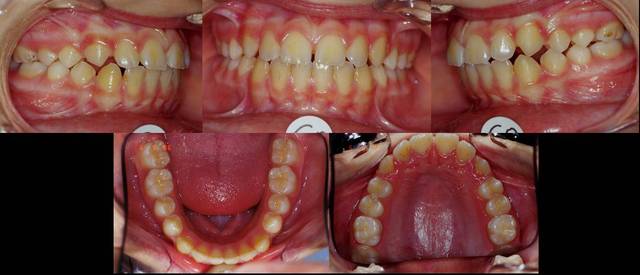

Motif :demande de la patiente

son profil ne lui plait pas

cas traité par A. Bagden, présenté en 2005